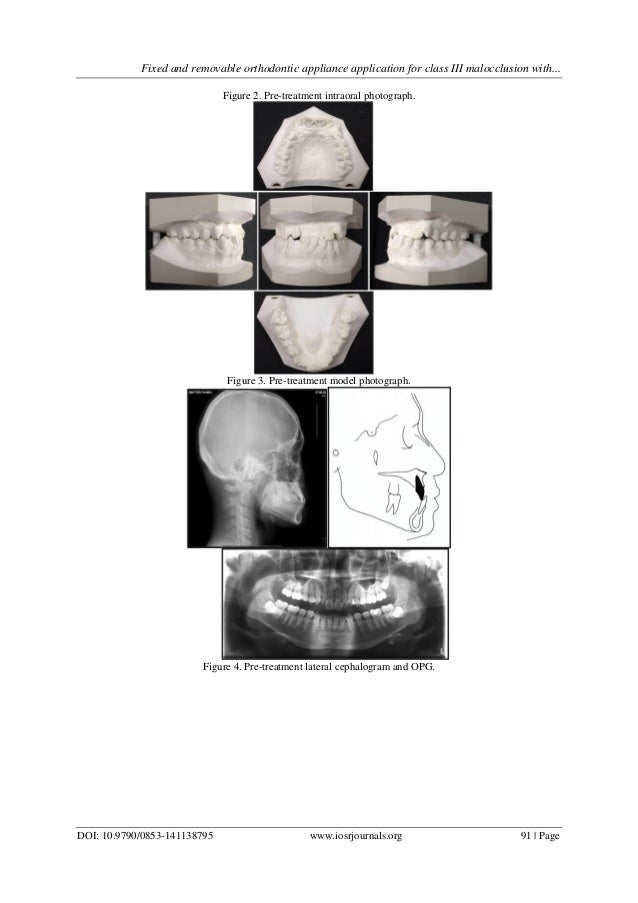

Fixed and removable orthodontic appliance application for class III m… Orthodontic Appliances For Class 3 The carriere® motion class iii appliance is used for class iii patients, to correct class iii at the. A removable class iii traction appliance using elastics to produce the desired vector of force (figures 1a and 1b) was developed in the 1980’s to overcome issues of patient. The motion 3d class iii appliance is a minimally invasive appliance for treating. Orthodontic Appliances For Class 3.